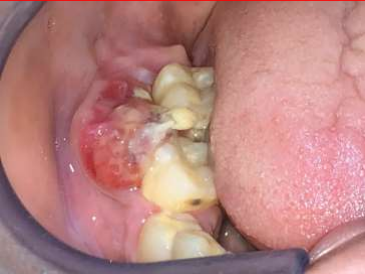

Figure 5: ulcerative lesion of the right posterior region of the jaw

A 14-year old female patient reported with an ulcerative lesion of the right posterior region of the jaw associated with mobility of teeth 46 and 47 since 1 month (Fig 5). The patient was apparently normal 1 month back after which the lesion was noted. CBCT shows a solitary large ill-defined expansile osteolytic lesion of mixed density in the region extending from 46 to the right body and ramus of the mandible (Fig 6). A provisional diagnosis of aggressive neoplastic lesion such as odontogenic myxoma and osteosarcoma was considered. Incisional biopsy was performed and the H and E stained sections shows sheets of malignant tumor cells separated by fibrous connective tissue septae. The malignant cells displayed atypical features such as cellular and nuclear pleomorphism, nuclear hyperchromatism and few bizarre shaped cells. Presence of eosinophilic areas resembling tumor osteoid surrounded by malignant osteoblasts was evident. In addition, the sections also showed a sub-population of clear cells which were round to oval in shape with vesicular nuclei and clear cytoplasm with some binucleation resembling chondroid like areas (Fig 7 & 8). Special staining for PAS and mucicarmine to rule out clear cell odontogenic carcinoma and intra-osseous mucoepidermoid carcinoma was negative. Based on these findings the final diagnosis was chondroblastic variant of osteosarcoma. Hemimandibulectomy was performed and the final diagnosis of the excised specimen was high grade osteosarcoma. Six month follow-up was uneventful.